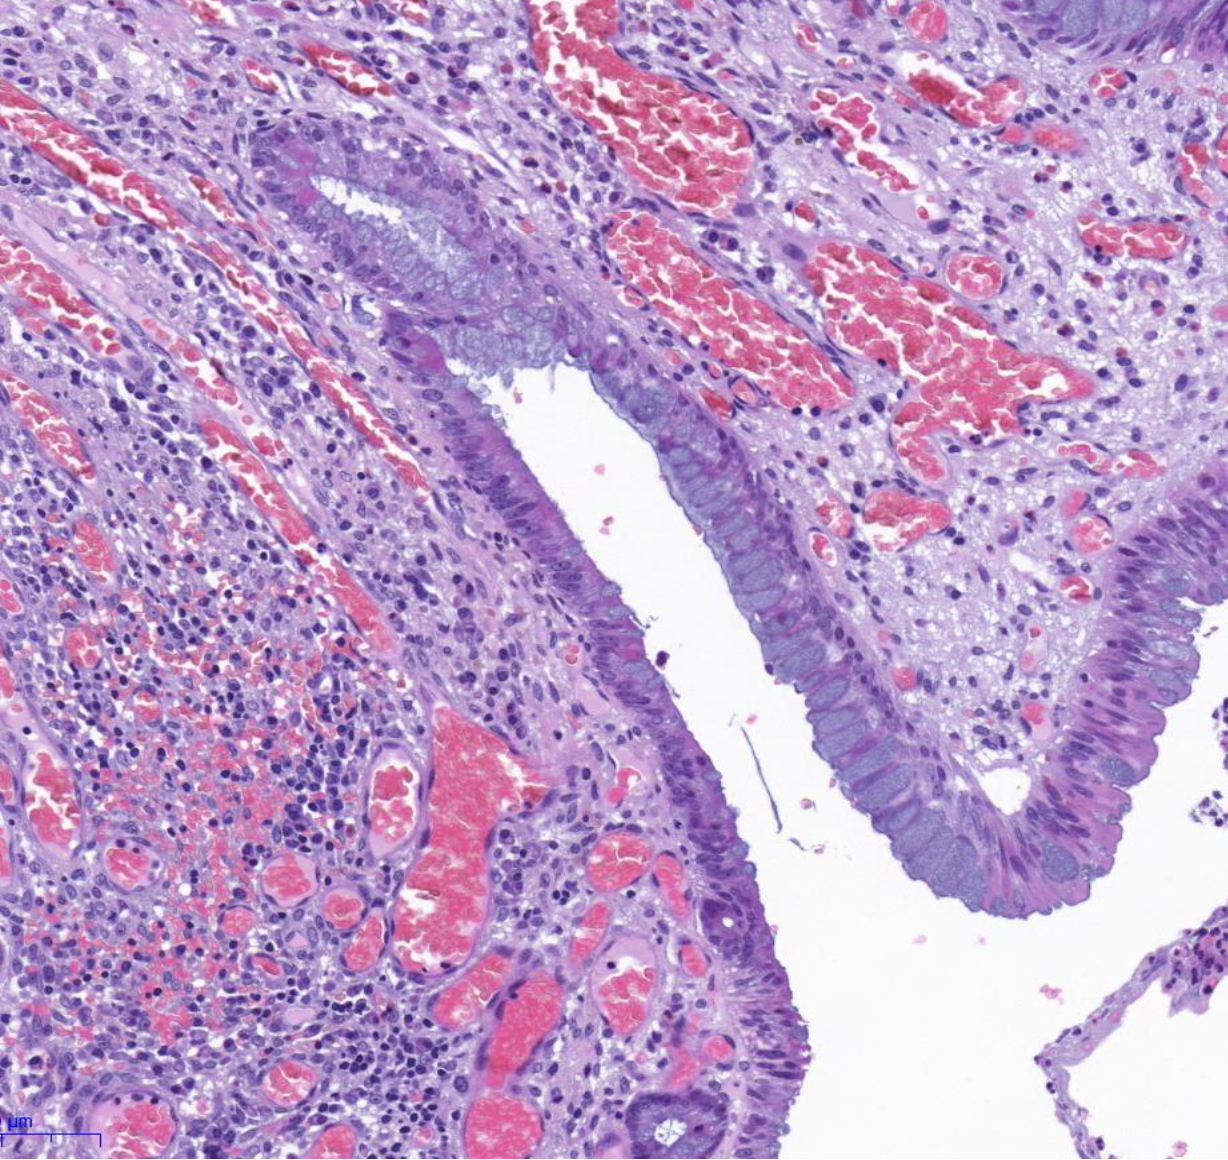

Diagnose?

Barettmetaplasie (dunkelviolett = mit Dysplasie)

Durch Reflux -> Metaplasie (nicht maligne) der Epithelien, intestinalisiertes Epithel/ Becherzellen, Biopsate mit Plattenepithel und Zylinderepithel (nur dann weiß man es ist Übergangsbereich)

Barrett-Zelle = Becherzelle